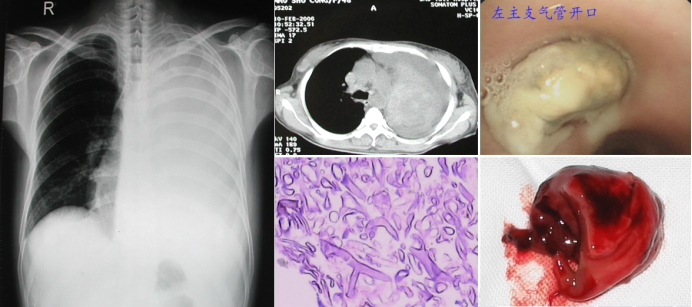

病例2:一例糖尿病酮症酸中毒合并肺毛霉感染患者,病情进展迅猛。此类感染具有显著的特征性表现:与普通细菌感染所致肺炎仅形成肺部阴影不同,毛霉等真菌感染可在肺内或气道中形成侵袭性新生物(图2),这种由大量毛霉菌丝构成的病变组织,相当于在体内生长的"异常生命体"。曾有呼吸科医师曾尝试通过介入技术清除此类病灶,但该操作风险极高。例如本例患者在介入过程中发生大出血,最终死亡。

图片

图2  病例2影像学、病理、气管镜下表现